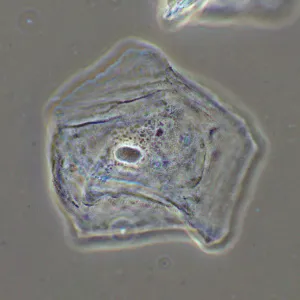

Фазово-контрастное устройство MAGUS SPH2 – это набор аксессуаров, которые позволяют реализовать на микроскопе MAGUS метод фазово-контрастной микроскопии. Фазовый контраст применяют для изучения прозрачных объектов, слабо различимых в светлом поле. Этот метод не требует окрашивания, повреждающего структуру живых образцов, поэтому подходит для широкого круга медицинских и фармакологических исследований.